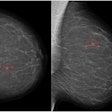

International team pinpoints causes of missed breast cancers